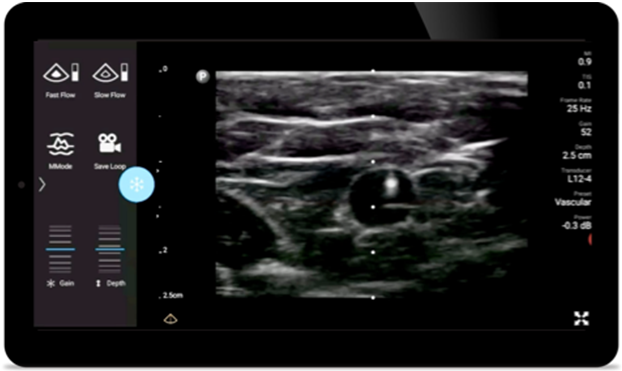

Improve precise placement on visually defined nerve blocks, so you can get in and out faster. And perform quick and thorough post-operative follow ups.

Lumify handheld ultrasound for anesthesiology helps you clearly visualize border definition with your needle placement, surrounding nerves, vessels and fascial planes.

Lumify helps you clearly visualize needle placement, surrounding nerves, vessels and fascial planes.

Lumify L12-4 broadband linear array transducer

• 12 to 4 MHz extended operating frequency range

• Aperture size: 34mm

• 2D, steerable color Doppler, M-mode, advancedXRES and multivariate harmonic imaging, SonoCT

• High resolution imaging for shallow applications: soft tissue, vascular, superficial, musculoskeletal and lung

• Center line marker

• USB-C transducer with replaceable cable